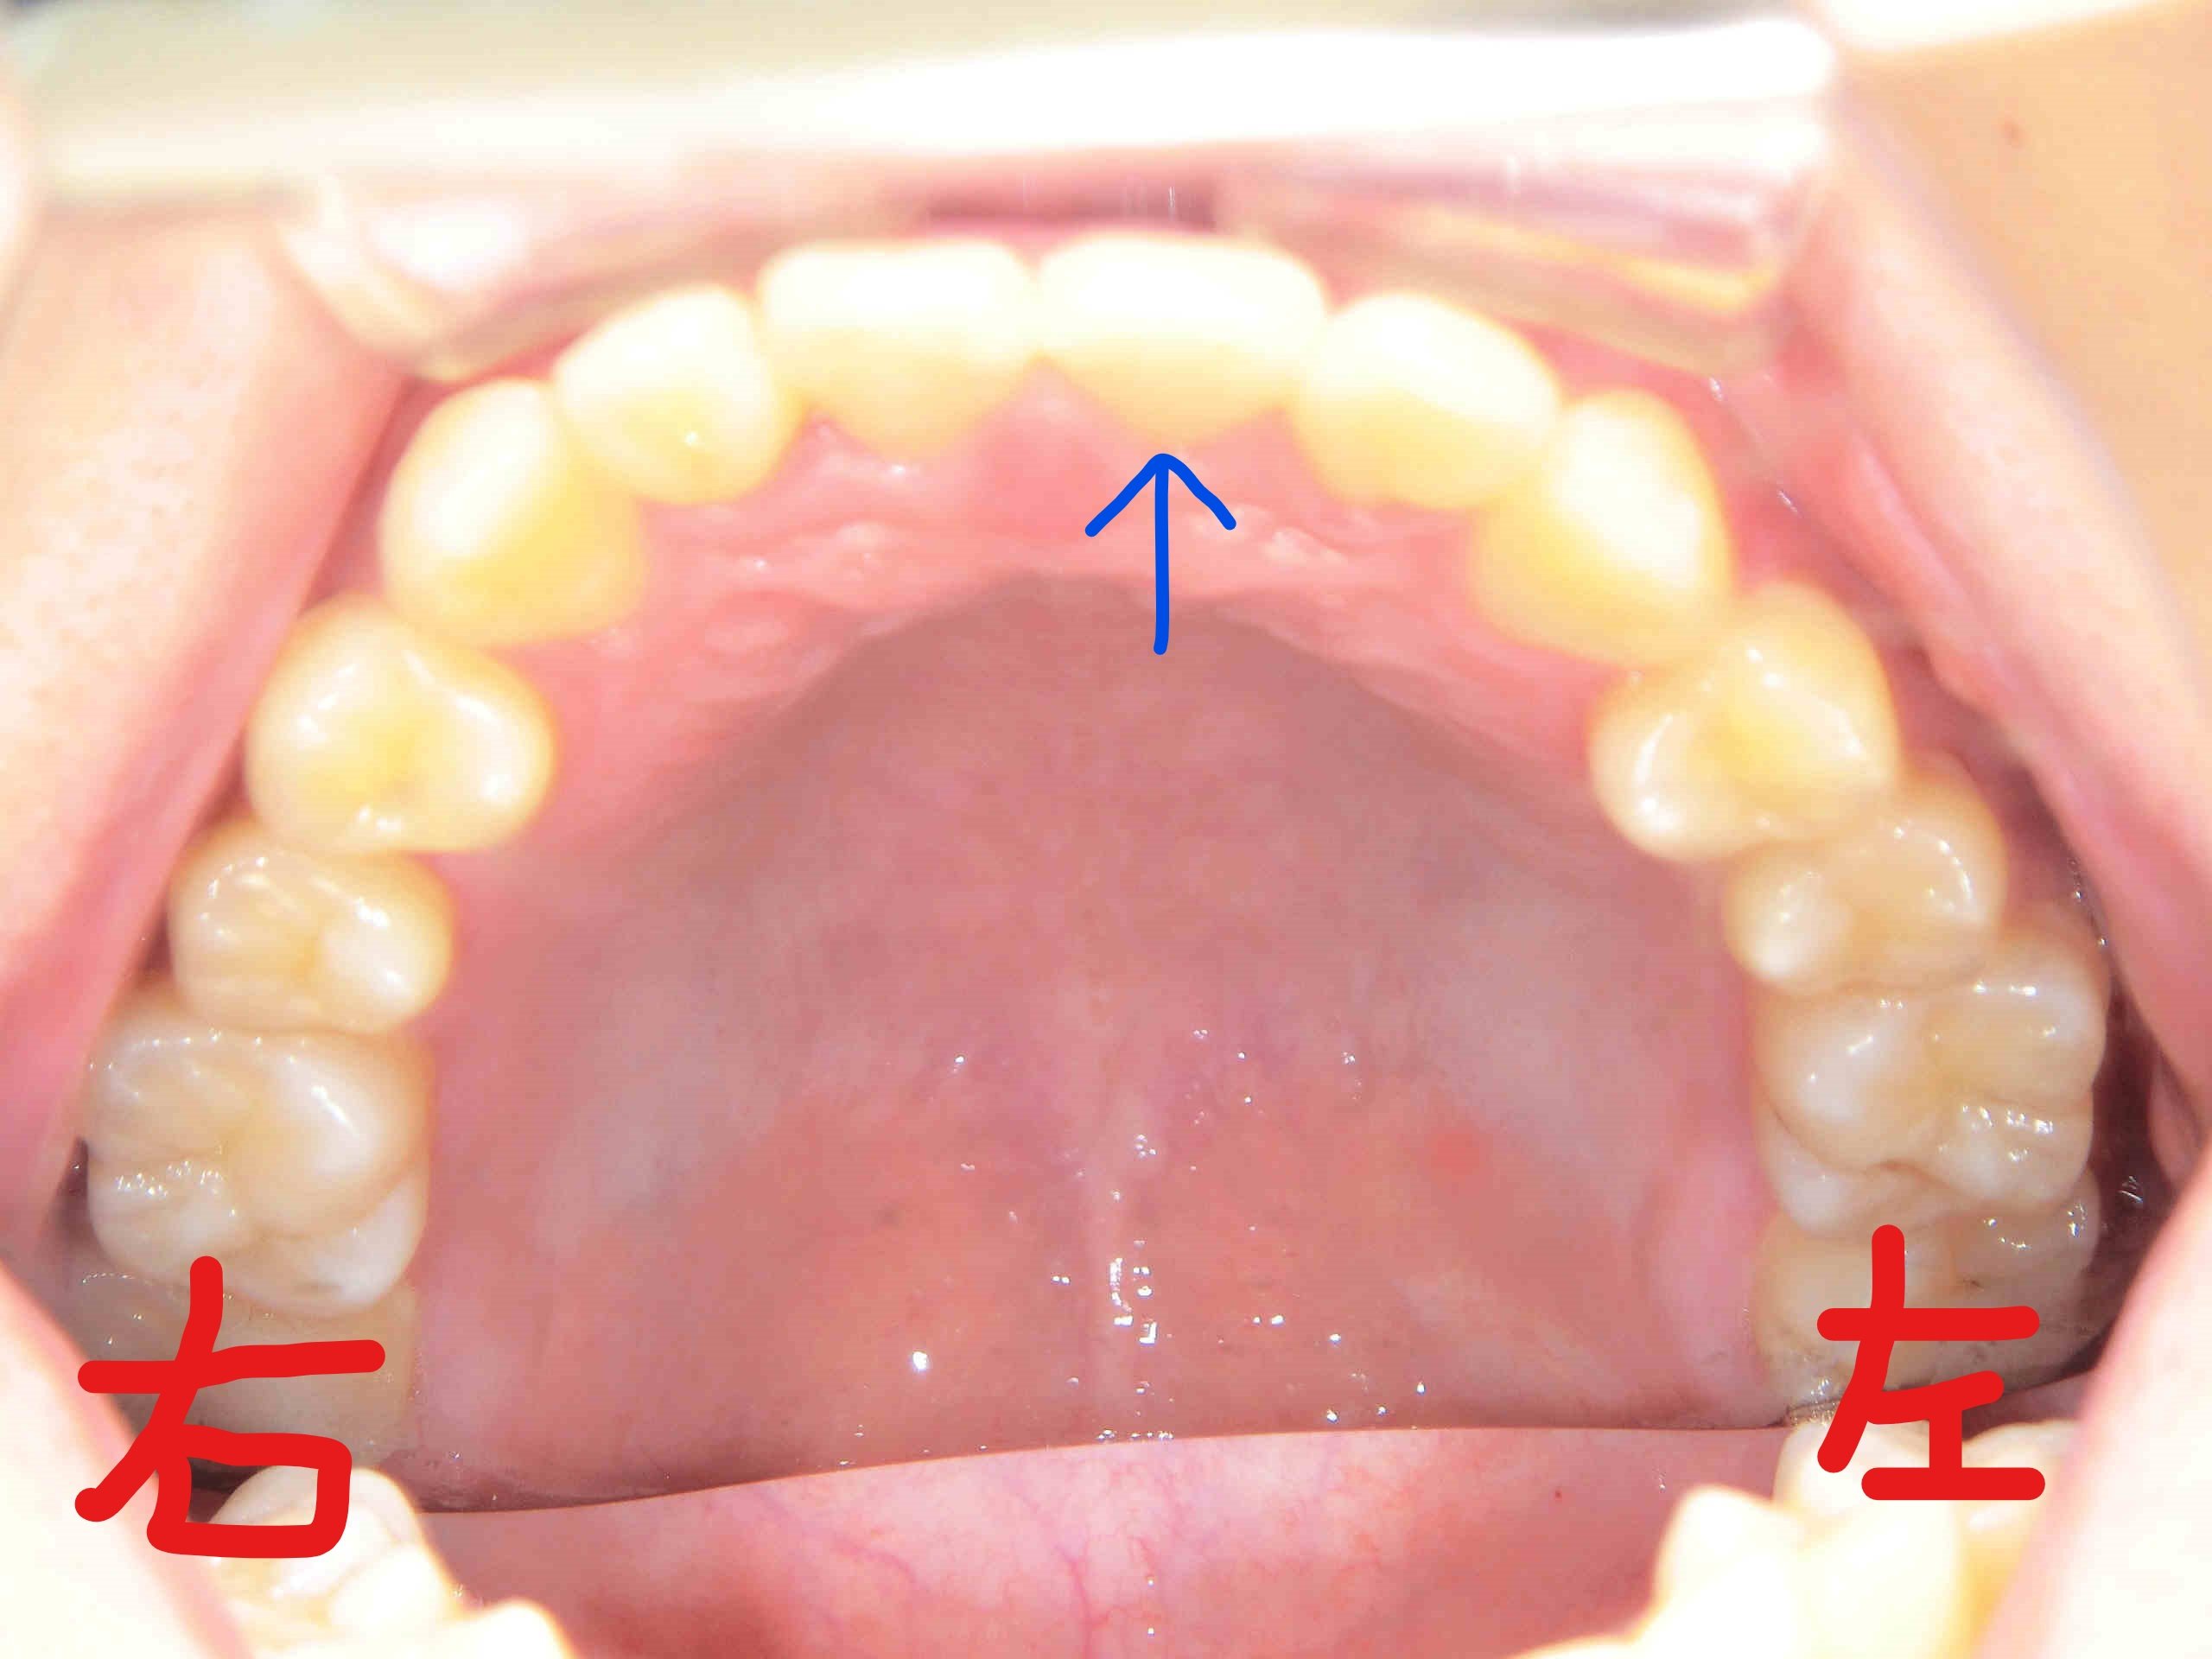

患者様は、左上の前歯(青色矢印)の“歪み(捻転)”を以前から気にされており、当院まで遠方よりご来院くださいました。

左上の写真は、上顎前歯にブラケット(ボタン)を装着した直後の状態、右上がブラケット装着前に上顎を下から見上げた写真です。主訴である左上の前歯がかなり捻転している様子がご確認いただけると思います。

次に、左上がブラケットを撤去する直前の上顎を下から見上げた写真、右上がブラケット撤去直後の写真です。青色矢印の歯にご注目ください。左上の前歯の捻転がしっかりと改善されているのがお分かりいただけると思います。